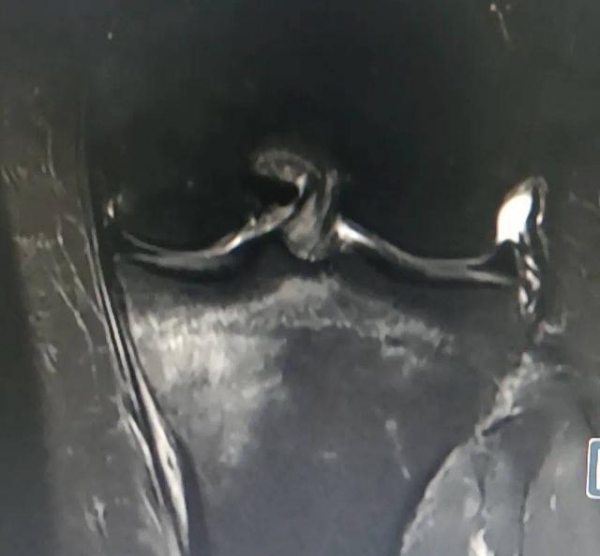

没想到第二天一起床,左腿瘸了。到成都市第一人民医院检查,医生考虑丁女士为胫骨上端疲劳骨折。

丁女士胫骨上端疲劳骨折图。医院供图